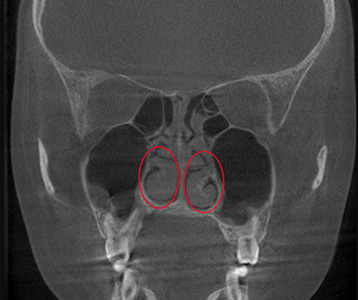

CT, 문진, 내시경, 후각, 음향,

통기도 검사 진행.

현재 상태를 정확히 분석합니다.